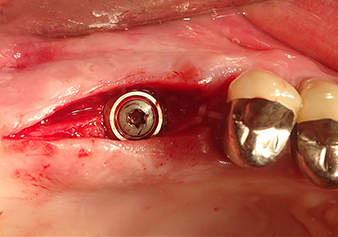

L’insert I2A (diamètre 2,0 mm) est ensuite utilisé pour perforer le plancher sinusien par intermittence et à la plus petite échelle possible. Cette méthode piézochirurgicale spéciale garantit que la membrane de Schneider n’est pas endommagée. Quand le Z25P est utilisé, la membrane est déjà légèrement relevée sous l’effet du fluide de refroidissement délivré via la pointe de l’insert (Fig. 3). Seulement 50 % du fluide de refroidissement sont éjectés afin d'éviter une pression élevée sur le site implantaire.